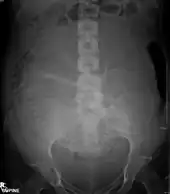

Projectional radiographs

Projectional radiography is the practice of producing two-dimensional images using X-ray radiation. Bones contain a high concentration of calcium, which, due to its relatively high atomic number, absorbs X-rays efficiently. This reduces the amount of X-rays reaching the detector in the shadow of the bones, making them clearly visible on the radiograph. The lungs and trapped gas also show up clearly because of lower absorption compared to tissue, while differences between tissue types are harder to see.

Projectional radiographs are useful in the detection of pathology of the skeletal system as well as for detecting some disease processes in soft tissue. Some notable examples are the very common chest X-ray, which can be used to identify lung diseases such as pneumonia, lung cancer, or pulmonary edema, and the abdominal x-ray, which can detect bowel (or intestinal) obstruction, free air (from visceral perforations), and free fluid (in ascites). X-rays may also be used to detect pathology such as gallstones (which are rarely radiopaque) or kidney stones which are often (but not always) visible. Traditional plain X-rays are less useful in the imaging of soft tissues such as the brain or muscle. One area where projectional radiographs are used extensively is in evaluating how an orthopedic implant, such as a knee, hip or shoulder replacement, is situated in the body with respect to the surrounding bone. This can be assessed in two dimensions from plain radiographs, or it can be assessed in three dimensions if a technique called '2D to 3D registration' is used. This technique purportedly negates projection errors associated with evaluating implant position from plain radiographs.[104]